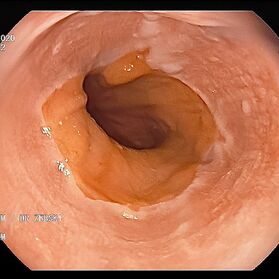

Mit einer Gastroskopie werden Speiseröhre, Magen und Zwölfingerdarm (der oberste Teil des Dünndarms) untersucht. Dazu wird ein geschmeidig biegsames, schlankes Endoskop mit eingebauter Digitalkamera durch den Mund eingeführt. Minimalste Veränderungen können dabei gesehen werden, die im Röntgenbild oder einer Kernspintomographie (MRT) noch gar nicht erkannt werden. Im Vergleich zu anderen bildgebenden Untersuchungsverfahren ist bei der Endoskopie neben der wichtigen optischen Beurteilung auch die sofortige Möglichkeit gegeben, Gewebeproben aus auffälligen Bereichen zu entnehmen. Dazu wird eine kleine Spezialzange durch einen Kanal im Endoskop geschoben und die Probe ganz präzise aus dem entsprechenden Gewebe gewonnen. Da die Schleimhäute schmerzunempfindlich sind, spüren Sie davon nichts. Die Proben werden von Spezialisten mikroskopisch untersucht und ermöglichen dann eine zielgerichtete Therapie; zum Beispiel wenn eine Magenschleimhautentzündung durch eine chronische Infektion ausgelöst wird, die mit einer Antibiotikakur erfolgreich behandelt werden kann.